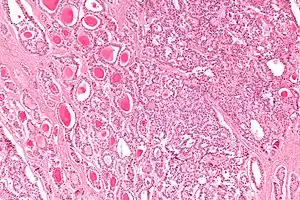

The strumal carcinoid is a type of monodermal teratoma with histomorphologic features of (1) the thyroid gland and (2) a neuroendocrine tumour (carcinoid).[1][2]

| Micrograph of a strumal carcinoid. H&E stain. |